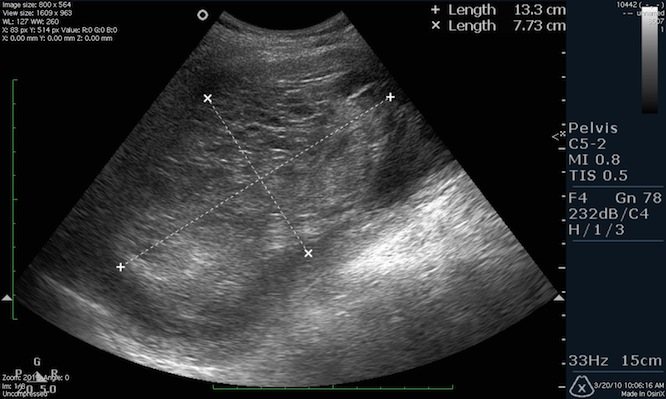

Ультразвуковое исследование покажет размеры матки, а опытный врач объяснит, каковы нормы ее размеров во время беременности, после родов и у девственниц. Фото УЗИ иллюстрирует размеры шейки матки, яичников и то, как выглядит матка, а врач даст полное описание изображению.

Ультразвуковое исследование является достоверным и доступным методом диагностики заболеваний органов репродуктивной системы. Во время проведения обследования врач определяет различные характеристики и размеры органа (матка, шейка матки, яичники). При выявлении отклонений от нормальных размеров матки и яичников во время УЗИ следует провести дополнительное тщательное обследование.